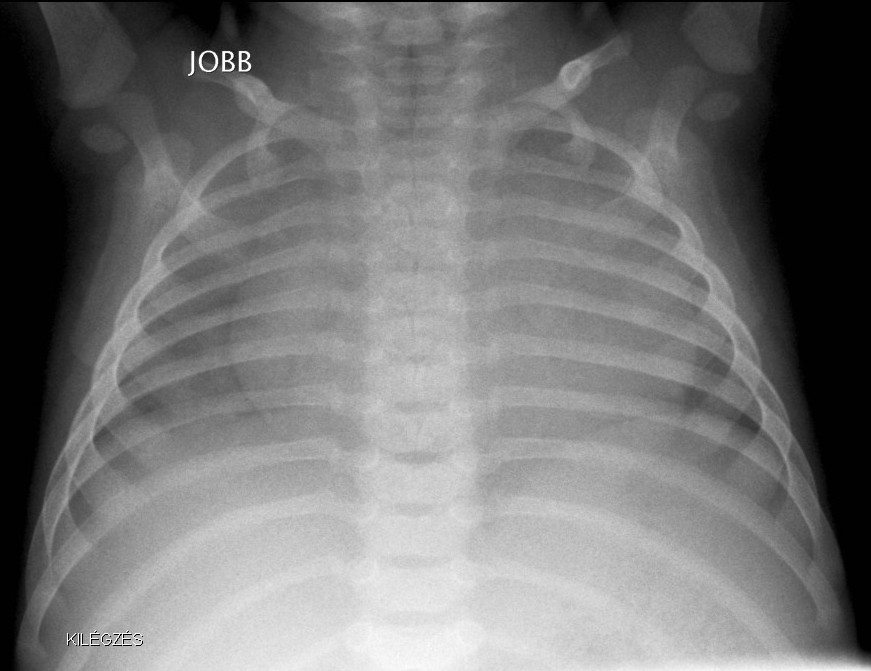

9.a At expiration the right side is expanded.

Image

9.b. At inspiration the midline is shifted to the right. Holzknecht sign: foreign body in the right bronchus

X-ray examination: aspirated foreign bodies are rarely X-ray absorbing, and therefore rarely appear on the radiographs. A negative inspiratory chest X-ray does not exclude the possibility of a FB aspiration. Most FBs cause occlusion on the level of the bronchi, which means that in inspiration air can get further than the FB but at expiration it will block the airway. Thus, on expiratory chest X-ray, the affected lung segment will be pneumatic; the diaphragm will be pushed lower on the ipsilateral side, while at inhalation the midline will be shifted towards the affected side (Holzknecht sign). In suspicion of FB aspiration (even if chest radiograph is negative) bronchoscopy is compulsory.